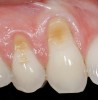

A 54-year-old non-smoking woman presented for correction of deep-wide gingival recession in the maxillary anterior (Figure 1 through Figure 3). The patient’s desires were to correct the gingival recession, balance the heights of contour of the tissues, and possibly undergo esthetic enhancement of the maxillary anterior with veneer restorations.

Figure 2  Case One Pretreatment clinical view, Case 1, maxillary anterior.

Figure 2